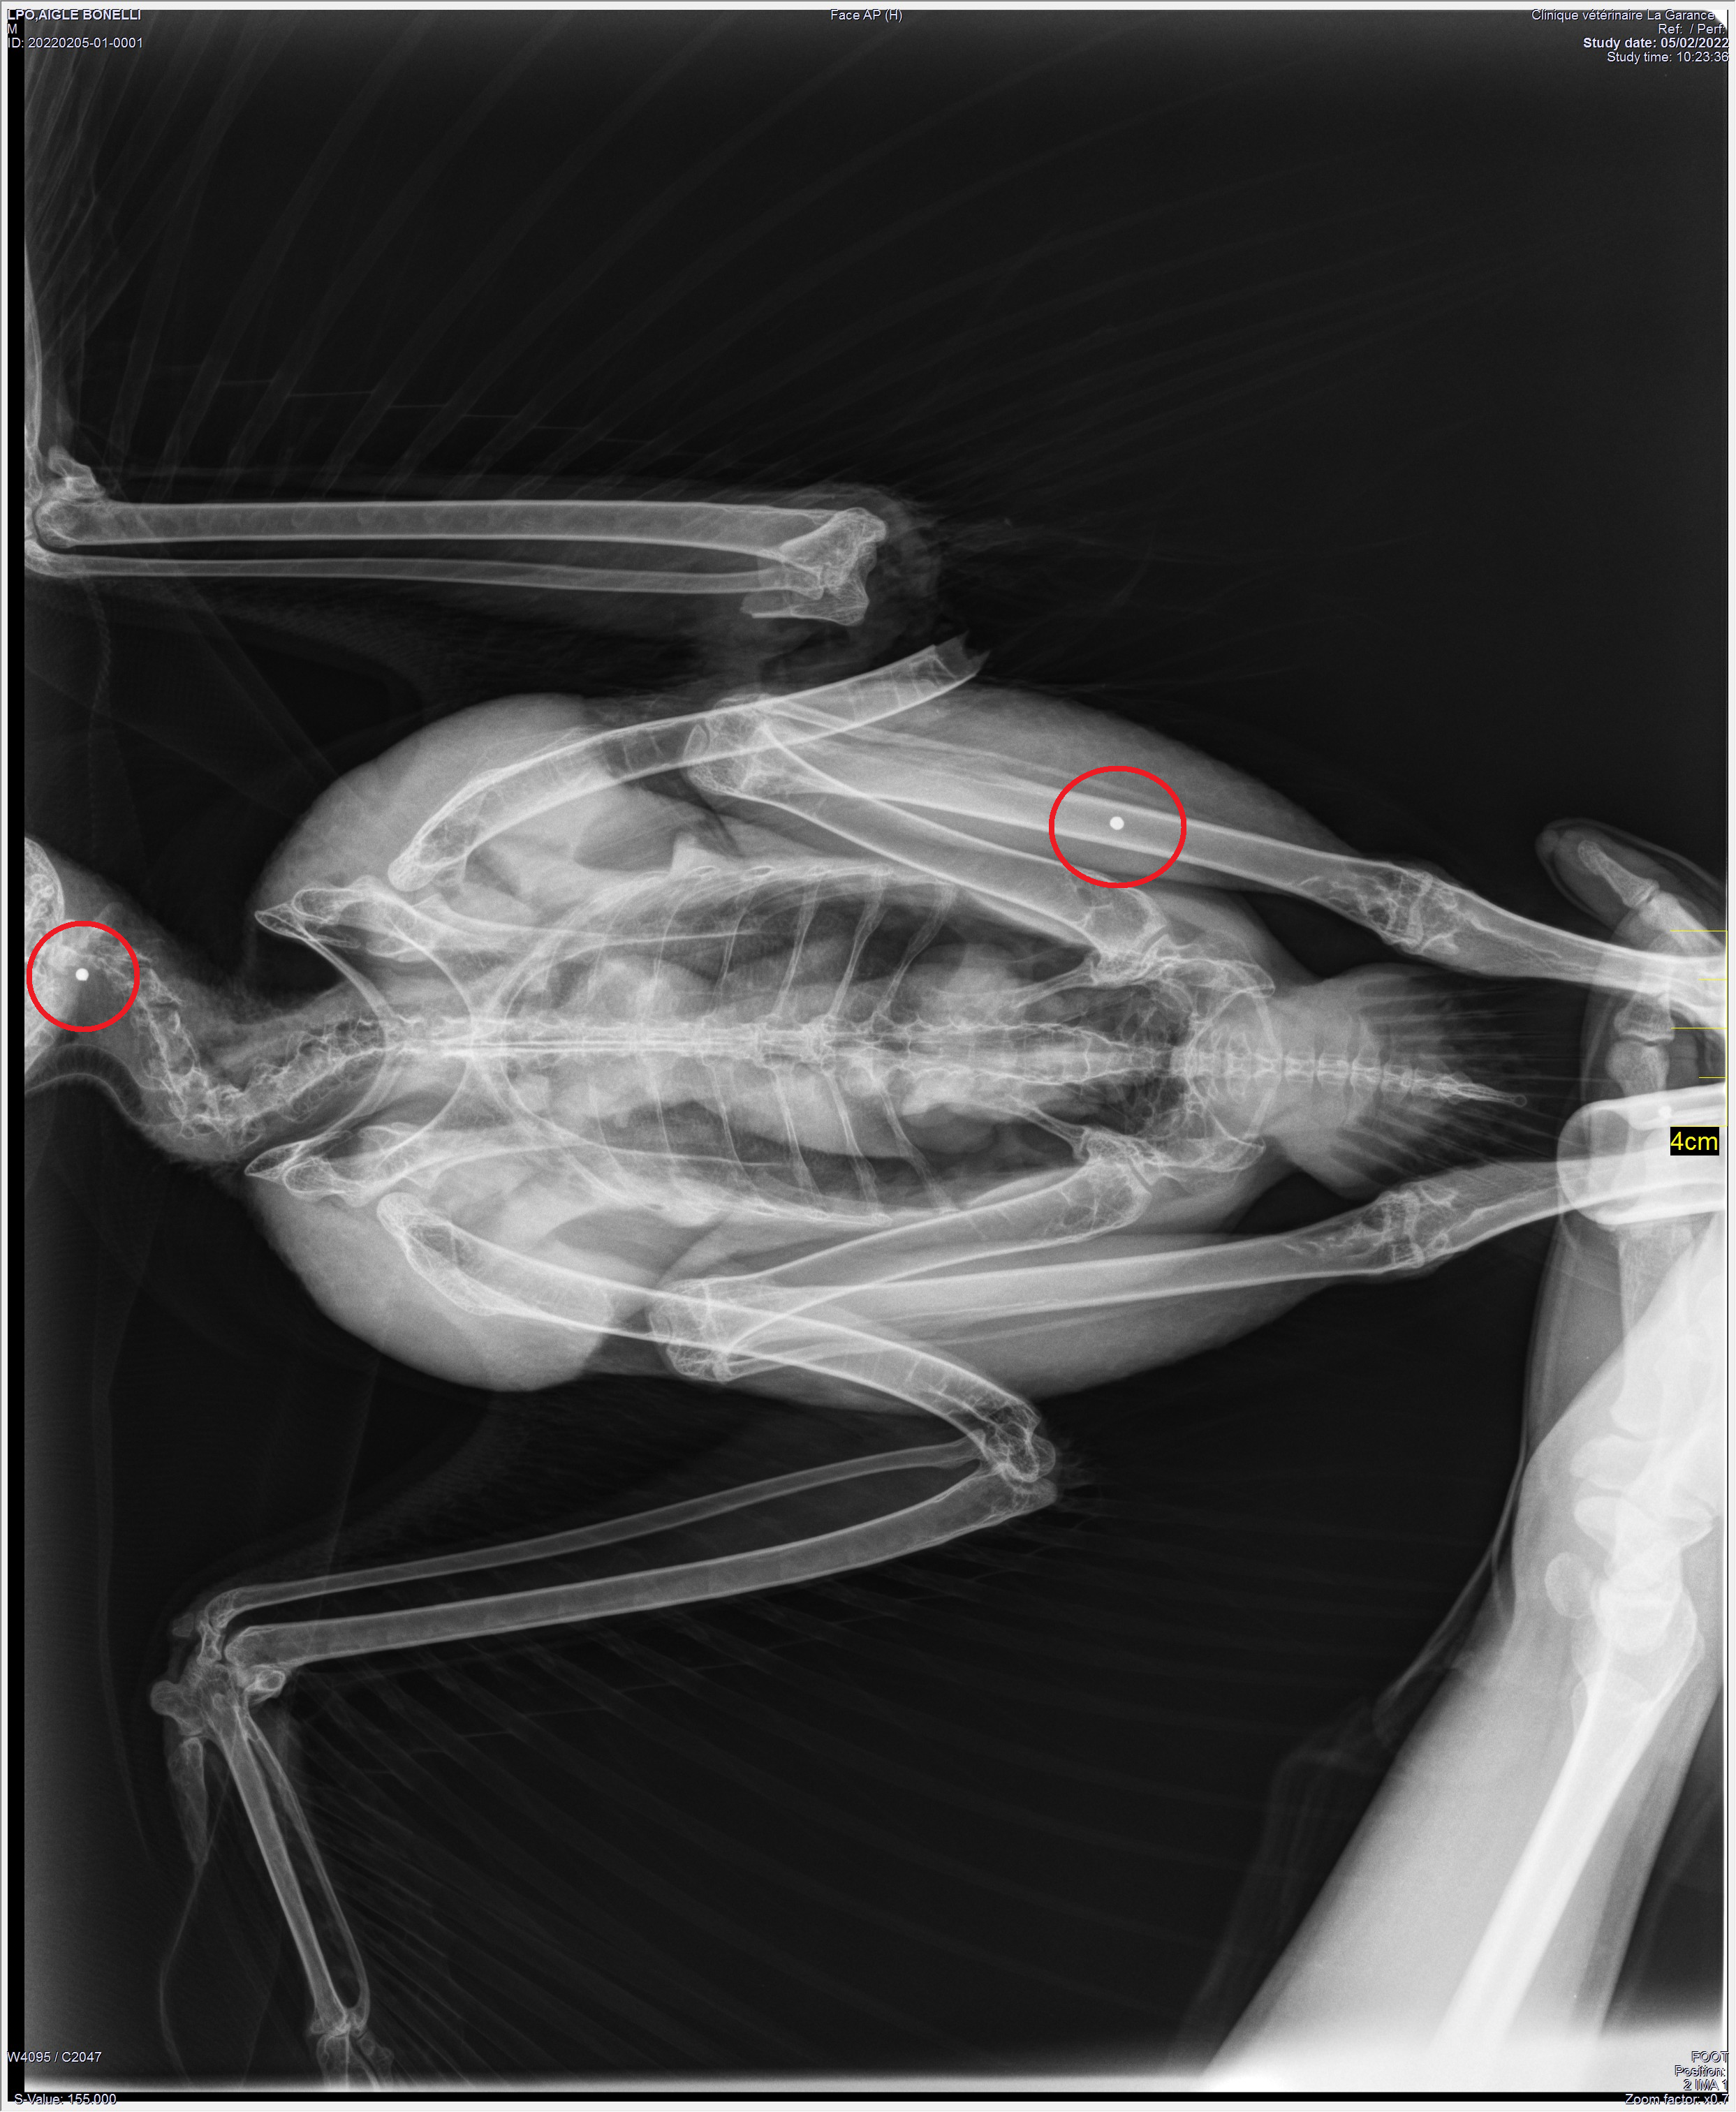

Sévèrement blessé à l’aile gauche (fracture ouverte de l’humérus), des radiographies de l’oiseau ont donc été réalisées par une clinique vétérinaire spécialisée, conformément au protocole de prise en charge des animaux du Centre régional de sauvegarde de la faune sauvage de la LPO PACA, en période de chasse. En effet, chaque rapace accueilli au centre entre les mois de septembre et de février bénéficie d’une radiographie afin de déceler ou non la présence de plombs. En 2021, la LPO PACA a ainsi recensé 25 oiseaux appartenant à des espèces protégées victimes de tirs illégaux, à savoir 9 Buses variables, 5 éperviers, 4 Faucons crécerelles, 1 Grandduc d’Europe, 1 Circaète Jean-le-Blanc, 1 Faucon pèlerin, 1 Vautour fauve, 1 Milan noir, 1 Héron cendré et 1 Choucas des tours.

Deux éclats de plomb ont été mis en évidence sur les radios de cet Aigle de Bonelli. Malgré la chirurgie osseuse pratiquée en urgence et les soins quotidiens qui lui ont été apportés, le rapace a succombé à ses blessures le 1er mars 2022. Chaque année, des animaux protégés sont victimes d’actes de braconnage (tir et empoisonnement), malgré les déclarations de tirs et les dépôts de plainte, les actes de destruction de ces oiseaux se poursuivent.